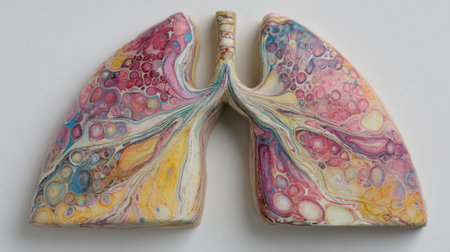

Anatomical model of human lungs featuring vivid colors and intricate patterns, highlighting the complexity of the respiratory system in an educational display.